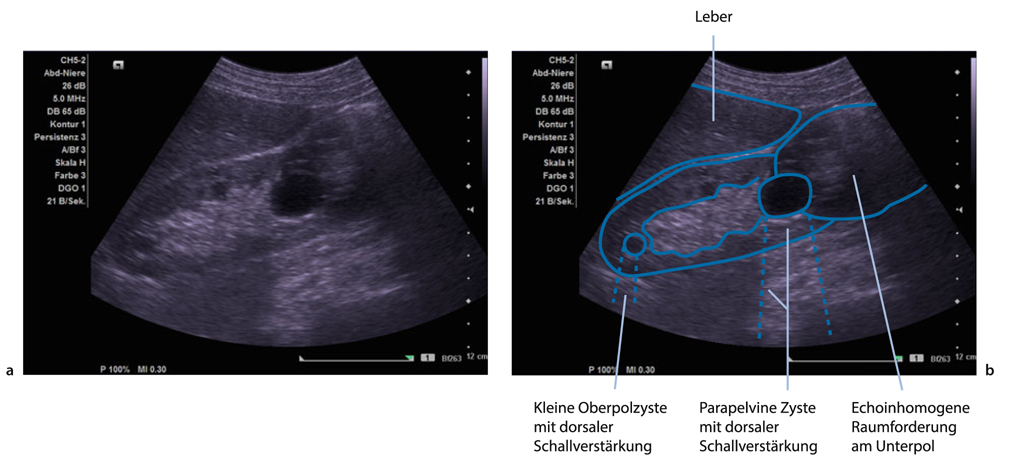

Unklare raumforderung an der linken niere diagnose bei einem 71 jährigen patienten wurde im rahmen einer vorsorgeuntersuchung beim hausarzt eine ultraschalluntersuchung der niere durchgeführt. Die häufigste raumforderung in der niere ist die einfache nierenzyste die meist 253 cm bereich 0510 cm durchmesser aufweist abb. Schau dir jetzt die ganze liste der weiteren möglichen ursachen und krankheiten an.